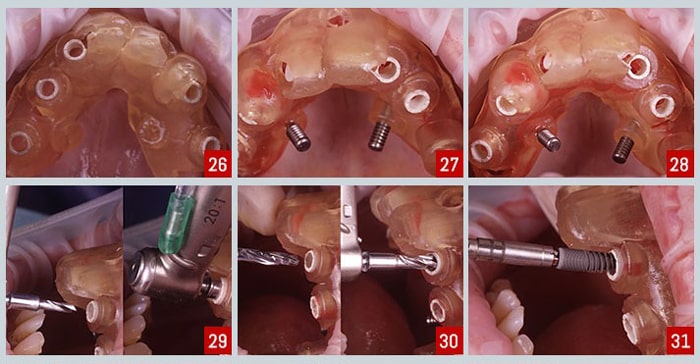

ایمپلنت دندان شامل چندین مرحله است: مشاوره و ارزیابی، جراحی کاشت فیکسچر، جوش خوردن ایمپلنت به استخوان، قرار دادن اباتمنت و نصب روکش. سخت ترین

ایمپلنت دندان با پیشرفت فناوری به دو نوع اصلی سنتی و دیجیتال تقسیم شده است. ایمپلنت سنتی به مهارت دندانپزشک و قالب گیری حضوری وابسته